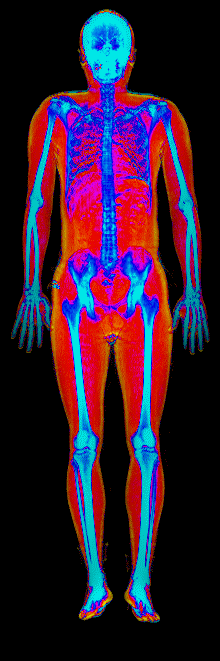

A DEXA scan passes two low-dose X-ray beams through your entire body, head to toe. Different tissues absorb different amounts of energy: bone absorbs the most, muscle and lean tissue less, and fat the least. The scanner reads how much energy made it through every pixel and assigns each one to a tissue type.

The colorful image at the top of every BodyStats DEXA report is literally that map. Bone shows up in cyan and white. Lean tissue is red. Fat is yellow and orange. Your body-fat percentage isn’t an inference — it’s a count of how much of that image is yellow and orange, broken out region by region: left arm vs right, left leg vs right, trunk, android (belly), gynoid (hips). And visceral fat — the dangerous abdominal fat that bioimpedance can’t see at all — comes back as its own number in cm².

This page features real, anonymized DEXA scan images from BodyStats clients, organized by gender and body fat percentage in 5% increments. DEXA (Dual-Energy X-ray Absorptiometry) is the clinical gold standard for measuring body composition — far more accurate than scales, calipers, or visual estimates.

Each colorized scan shows the distribution of fat tissue (shown in warmer colors) and lean tissue (cooler colors) throughout the body. Compare your own DEXA scan to others in your range, or see what different body fat levels actually look like on a scan.

Male DEXA Scans by Body Fat %

25 to 30% body fat